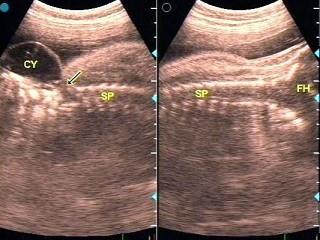

36周胎儿脊柱超声检查如图,根据声像图,初步诊断应该为?(?)A.血管瘤B.脑积水C.先天性蛛网膜囊肿D.脊膜膨出E.脊柱裂

问题 36周胎儿脊柱超声检查如图,根据声像图,初步诊断应该为?(?)

选项 A.血管瘤 B.脑积水 C.先天性蛛网膜囊肿 D.脊膜膨出 E.脊柱裂

答案 D